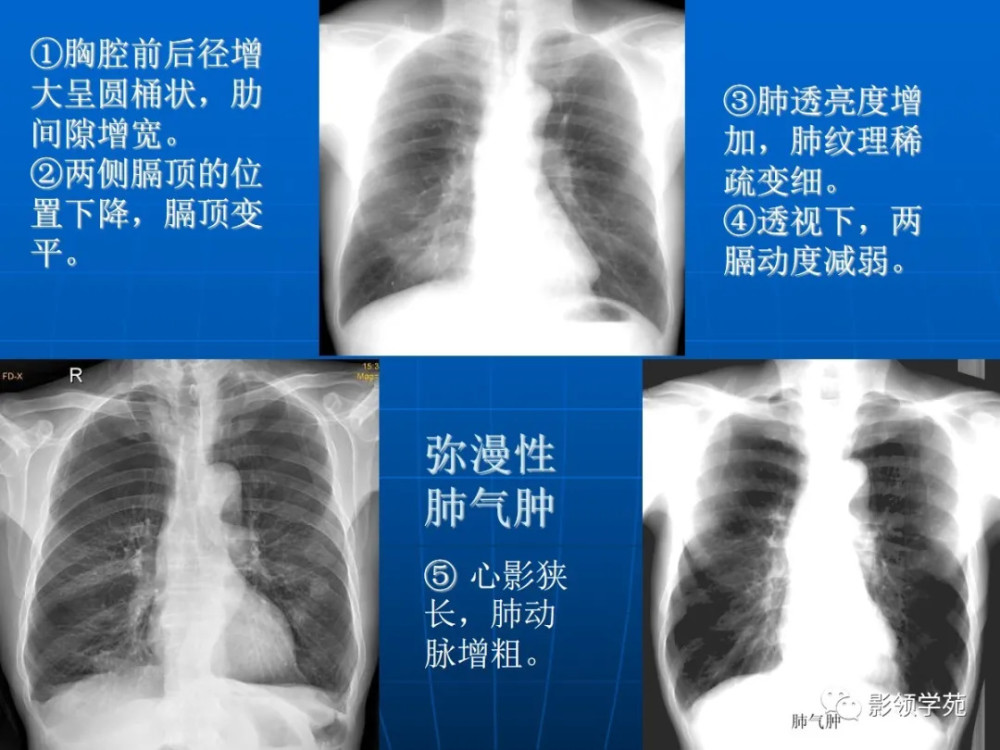

肺气肿胸片影像

肺气肿的胸片表现